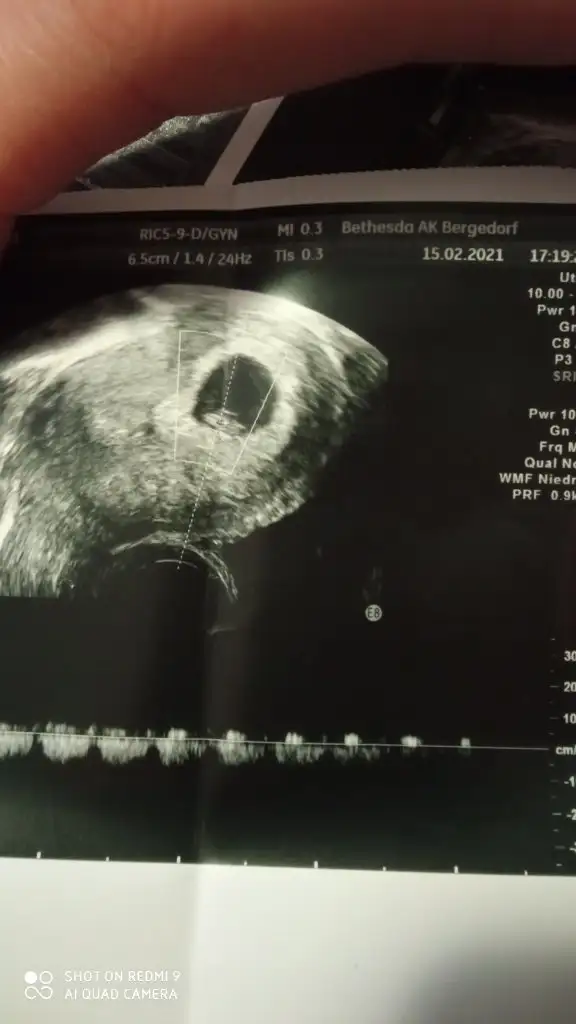

T Takitoki Benim bebeğim 8 haftalık vanija dan bakıldı sağda bebeğim cinsiyeti nedir

• IMG_20210215_192449.webp

18,7 KB · Görüntüleme: 140